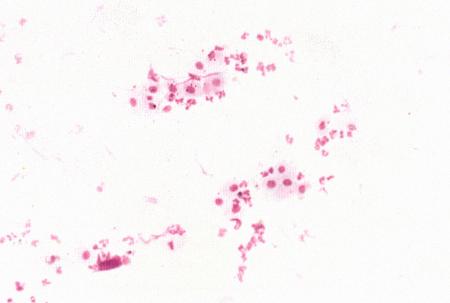

Фиг. 2.2.

Вагинальные выделения кошки (а). Выделения, типичные для фазы эструса. Большая часть клеток представляет собой безъядерные кератинизированные клетки или клетки с пикнотическим ядром. Присутствуют промежуточные клетки (b). Выделения, характерные для метэструса, — «течки», иногда наблюдаемой у кошек в конце эструса. Присутствуют поверхностные и промежуточные клетки, повышено содержание лейкоцитов. Этот короткий метэструс наблюдается в течение 24–48 часов (см. Приложение)